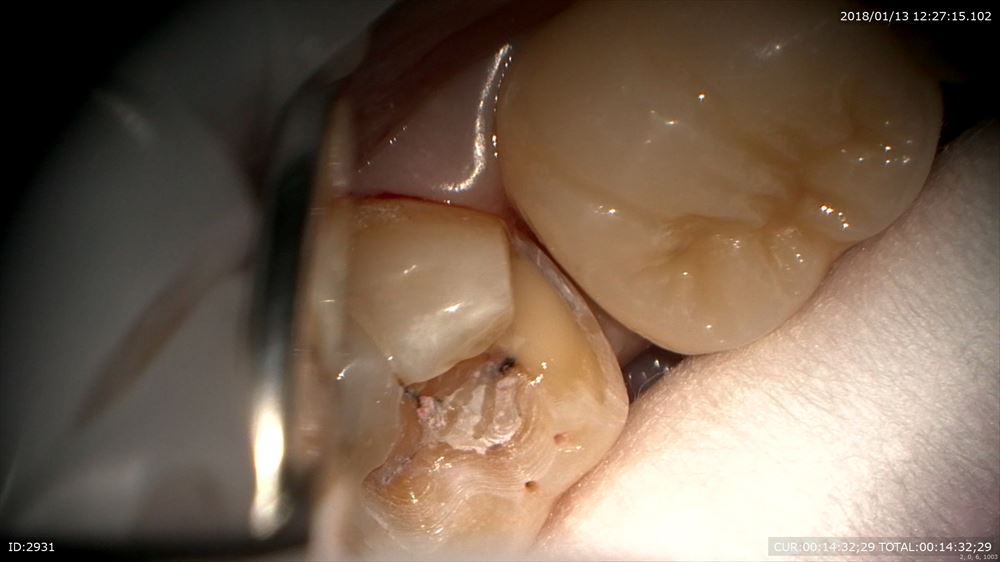

色々な人がきます。この方は他院で治療器具を残されたケース(根管治療に使う器具が根管の中で折れている)症状がなければまだ良いのですが。。症状があります。異物ですので確実に除去したい所です。今日は1時間半の格闘。超音波や色々な最新器具で隙間を器具と歯の間に作ります。0.1mmの世界。

光っているのが金属のリーマーです。

きたー。

嬉しい。今日はビールを飲もう!!

右が術前。左が術後